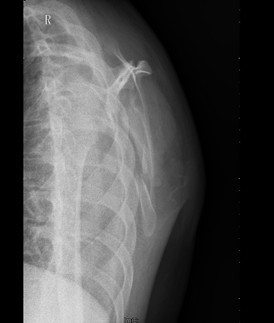

患者男,18岁,因“车祸伤致右肩部疼痛伴活动受限15天”入院。患者入院前15天乘坐摩托车时不慎发生车祸,伤及右侧肩部。伤后即往当地医院,诊断为右肩胛骨粉碎性骨折,行输液及对症治疗(具体不详),右绷带包扎固定,患者患者为求进一步治疗于今日来我院,门诊以右肩胛骨粉碎性骨折收入我科。

查体:右侧肩背部稍肿胀,局部皮肤无破溃。右肩背部触痛明显,右肘、右前臂、手部无明显触痛,无感觉减退,右桡动脉尺动脉搏动可扪及。右侧肩关节因疼痛拒动,右肘、右腕关节,手指活动无受限。左上肢及双下肢肌力正常、活动无受限。 辅查:X片、CT示右侧肩胛骨皮质连续性中段,骨折块移位,提示右肩粉碎性骨折。

诊断:右肩胛骨粉碎性骨折 治疗:拟行右肩胛骨骨折切开复位内固定术